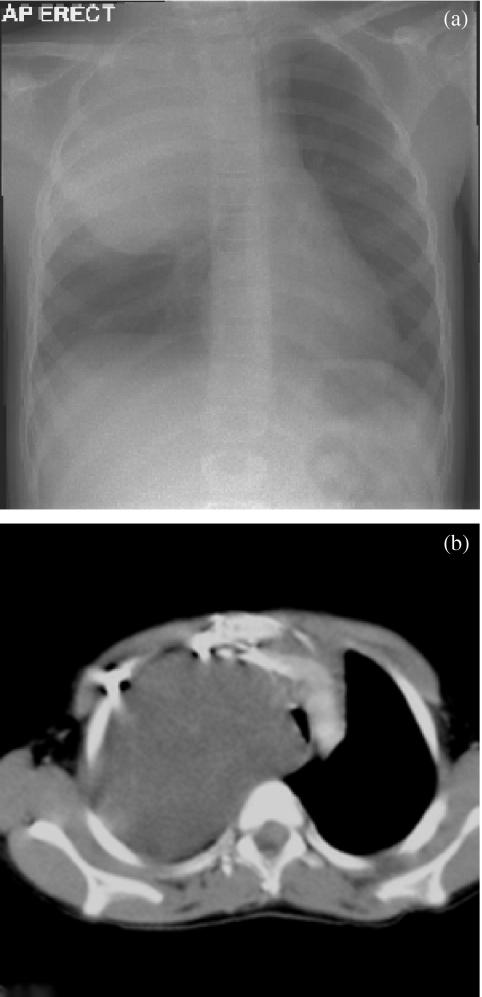

Bilateral adrenal cystic neuroblastoma with superior vena cava syndrome and massive intracystic haemorrhage.

Pediatr Radiol. 2004 Sep;34(9):746-9. doi: 10.1007/s00247-004-1209-5. Epub 2004 May 26.